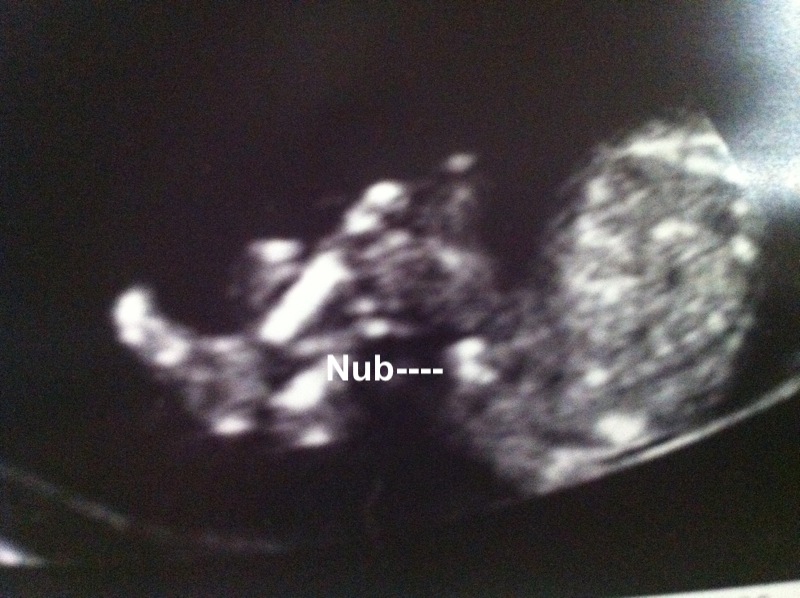

Here is my scan at 12w 4d but baby measured at 13w 1d baby would not sit still so couldnt get a clear shot i went through ultrasound and this is what i found would love to hear what you think thanks guys